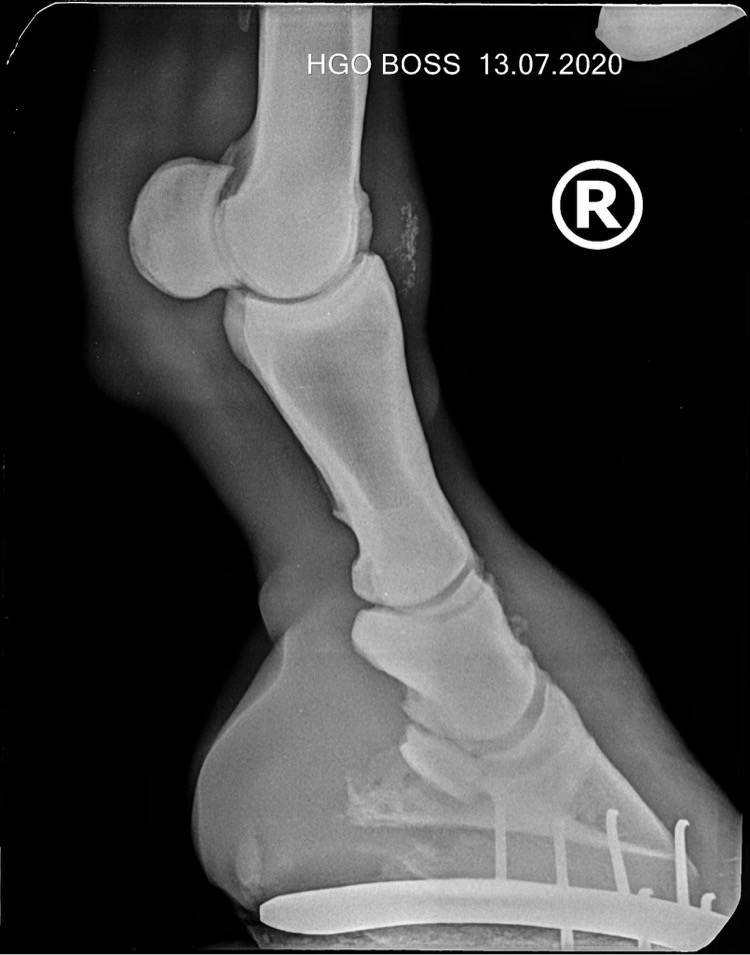

denis23 Опытный 13 Июль 2020 #2 вот рентгены. Вложения 85DB6103-3262-457A-9EC6-C11434451E2D.jpeg 108.6 KB · Просмотры: 196 14D59F73-6819-498E-83C4-FD2539AA5479.jpeg 109 KB · Просмотры: 189